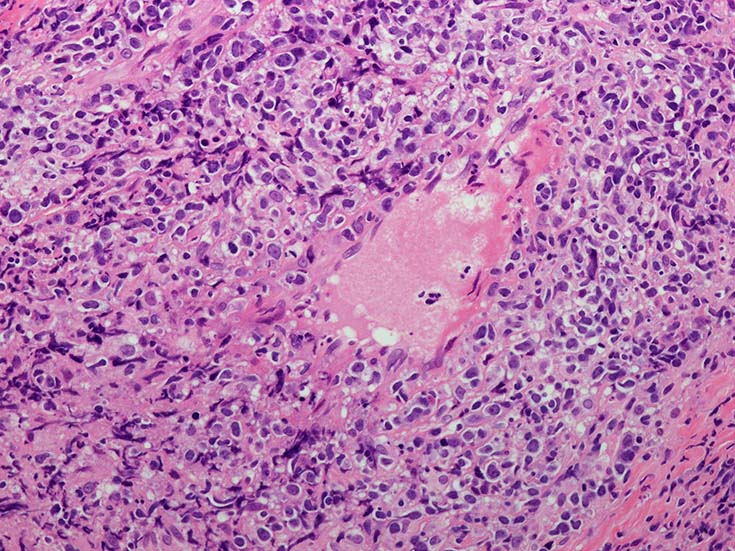

• 組織学的に,LyGは,様々な割合のリンパ球と大きなEBV+芽球からなる血管中心の浸潤を特徴としており,その中にはHRSに類似した特徴を示すものが出現する. 血管浸潤とそれに伴う多量の凝固壊死が典型的な所見である.

血管周囲性に大型類円形核や不整形核をもつ腫瘍細胞がシート状密に浸潤増殖している. Mitosisが多く認められる.細血管閉塞や破壊の所見がある.

間質にもシート状の腫瘍細胞浸潤がある. 大小 pleomorphicな傾向.(A, B). necrosisが認められる(C). 細気管支上皮直下まで密な浸潤あり, 小型リンパ球が混在している.(D)

血管中心性浸潤. 障害された血管内に血栓が形成されている.CD20陽性細胞がシート状密に浸潤, CD3陽性T細胞が多く混在している. EBER-ISH陽性 EBV感染細胞が多数認められ, >50 hpf, 定義より Grade3となる. 陽性細胞のサイズは大小さまざまであることに注意.